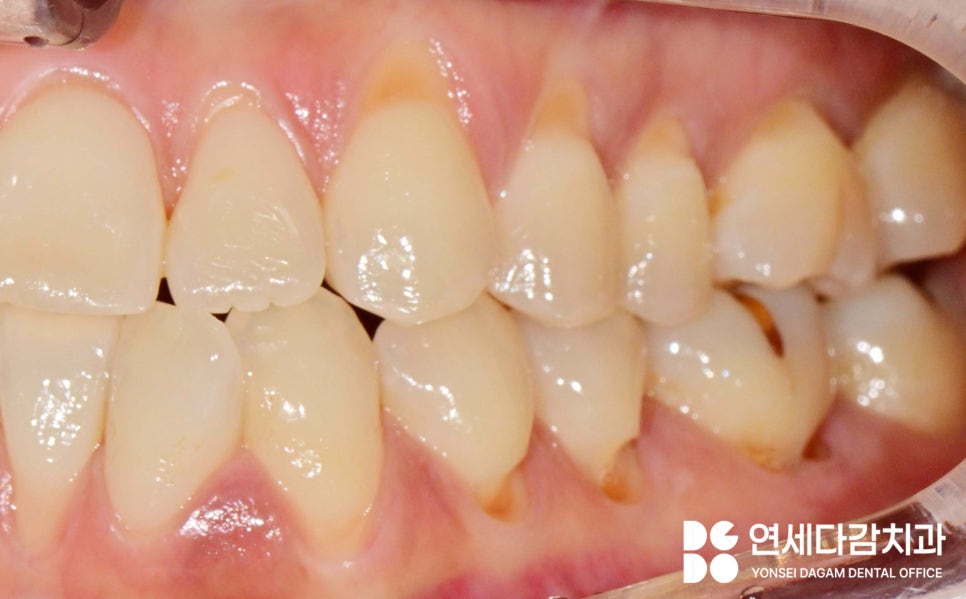

치아 미백 후에는 웃을 때 보이는

치경부 마모증 부위가

신경 쓰일 수밖에 없습니다.

문정역 치과 에서 표시한

부위를 살펴보면 이가 패어있는

형태인 것을 볼 수 있는데,

하얗게 된 치아와 대비되어

더욱 눈에 띄게 되는 경우가 많습니다.

웃을 때 잘 보이는 부위에는 레진을,

레진으로 수복한 부위는

실제로 자연치와 유사한 색상을 재현하여

심미적으로 안정적인 것을 볼 수 있습니다.

앞니 부위는 미소를 지을 때

잘 보이는 부분이므로

심미성을 우선시한 것입니다.